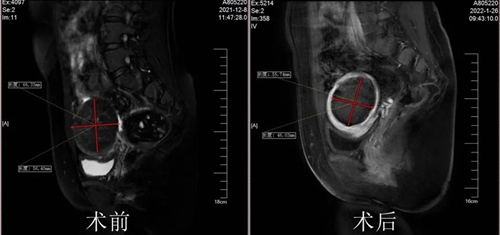

手術(shù)如期進(jìn)行,經(jīng)過一個(gè)半小時(shí)的海扶治療,有效消融了Rose女士子宮側(cè)壁最大的肌瘤和其他小肌瘤,同時(shí)內(nèi)膜、漿膜沒有一點(diǎn)損傷。看著自己的術(shù)后檢查結(jié)果,Rose女士心里的石頭終于落了地,24小時(shí)后恢復(fù)良好的她順利出院。